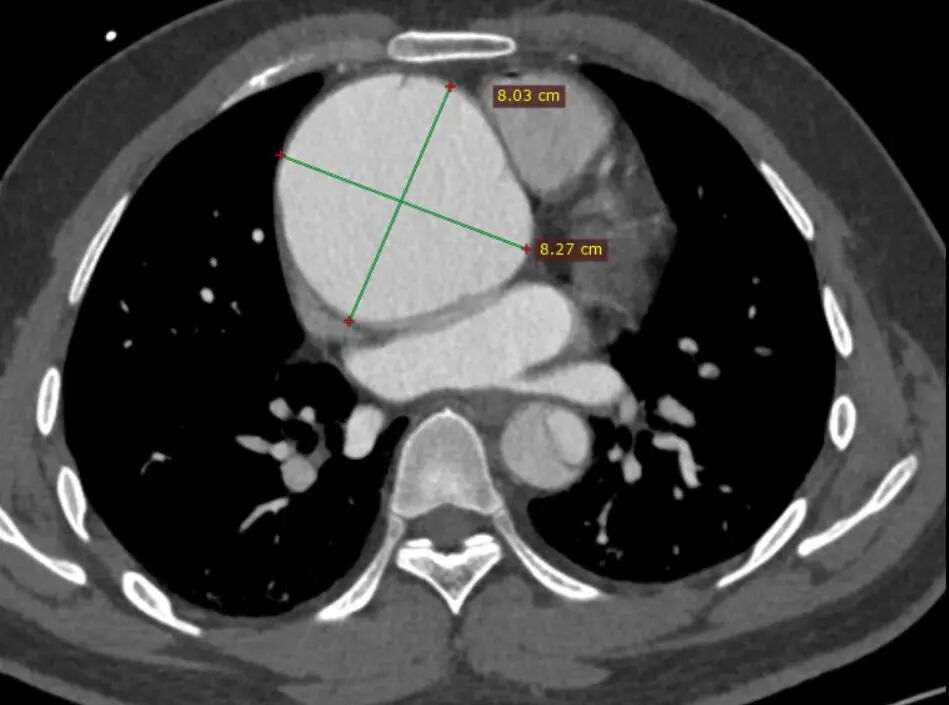

基本情况&CTA详解

患者男性,33岁,就诊6小时前出现剧烈胸部疼痛。患者既往无高血压、糖尿病等病史。于急诊科行全主动脉CTA检查。CTA提示患者B型夹层,破口紧邻左锁骨下动脉后缘,巨大升主动脉瘤,弓上三分支未受累及,左侧椎动脉优势。结合患者体征及家族史,推测为马凡综合征。

巨大升主动脉瘤